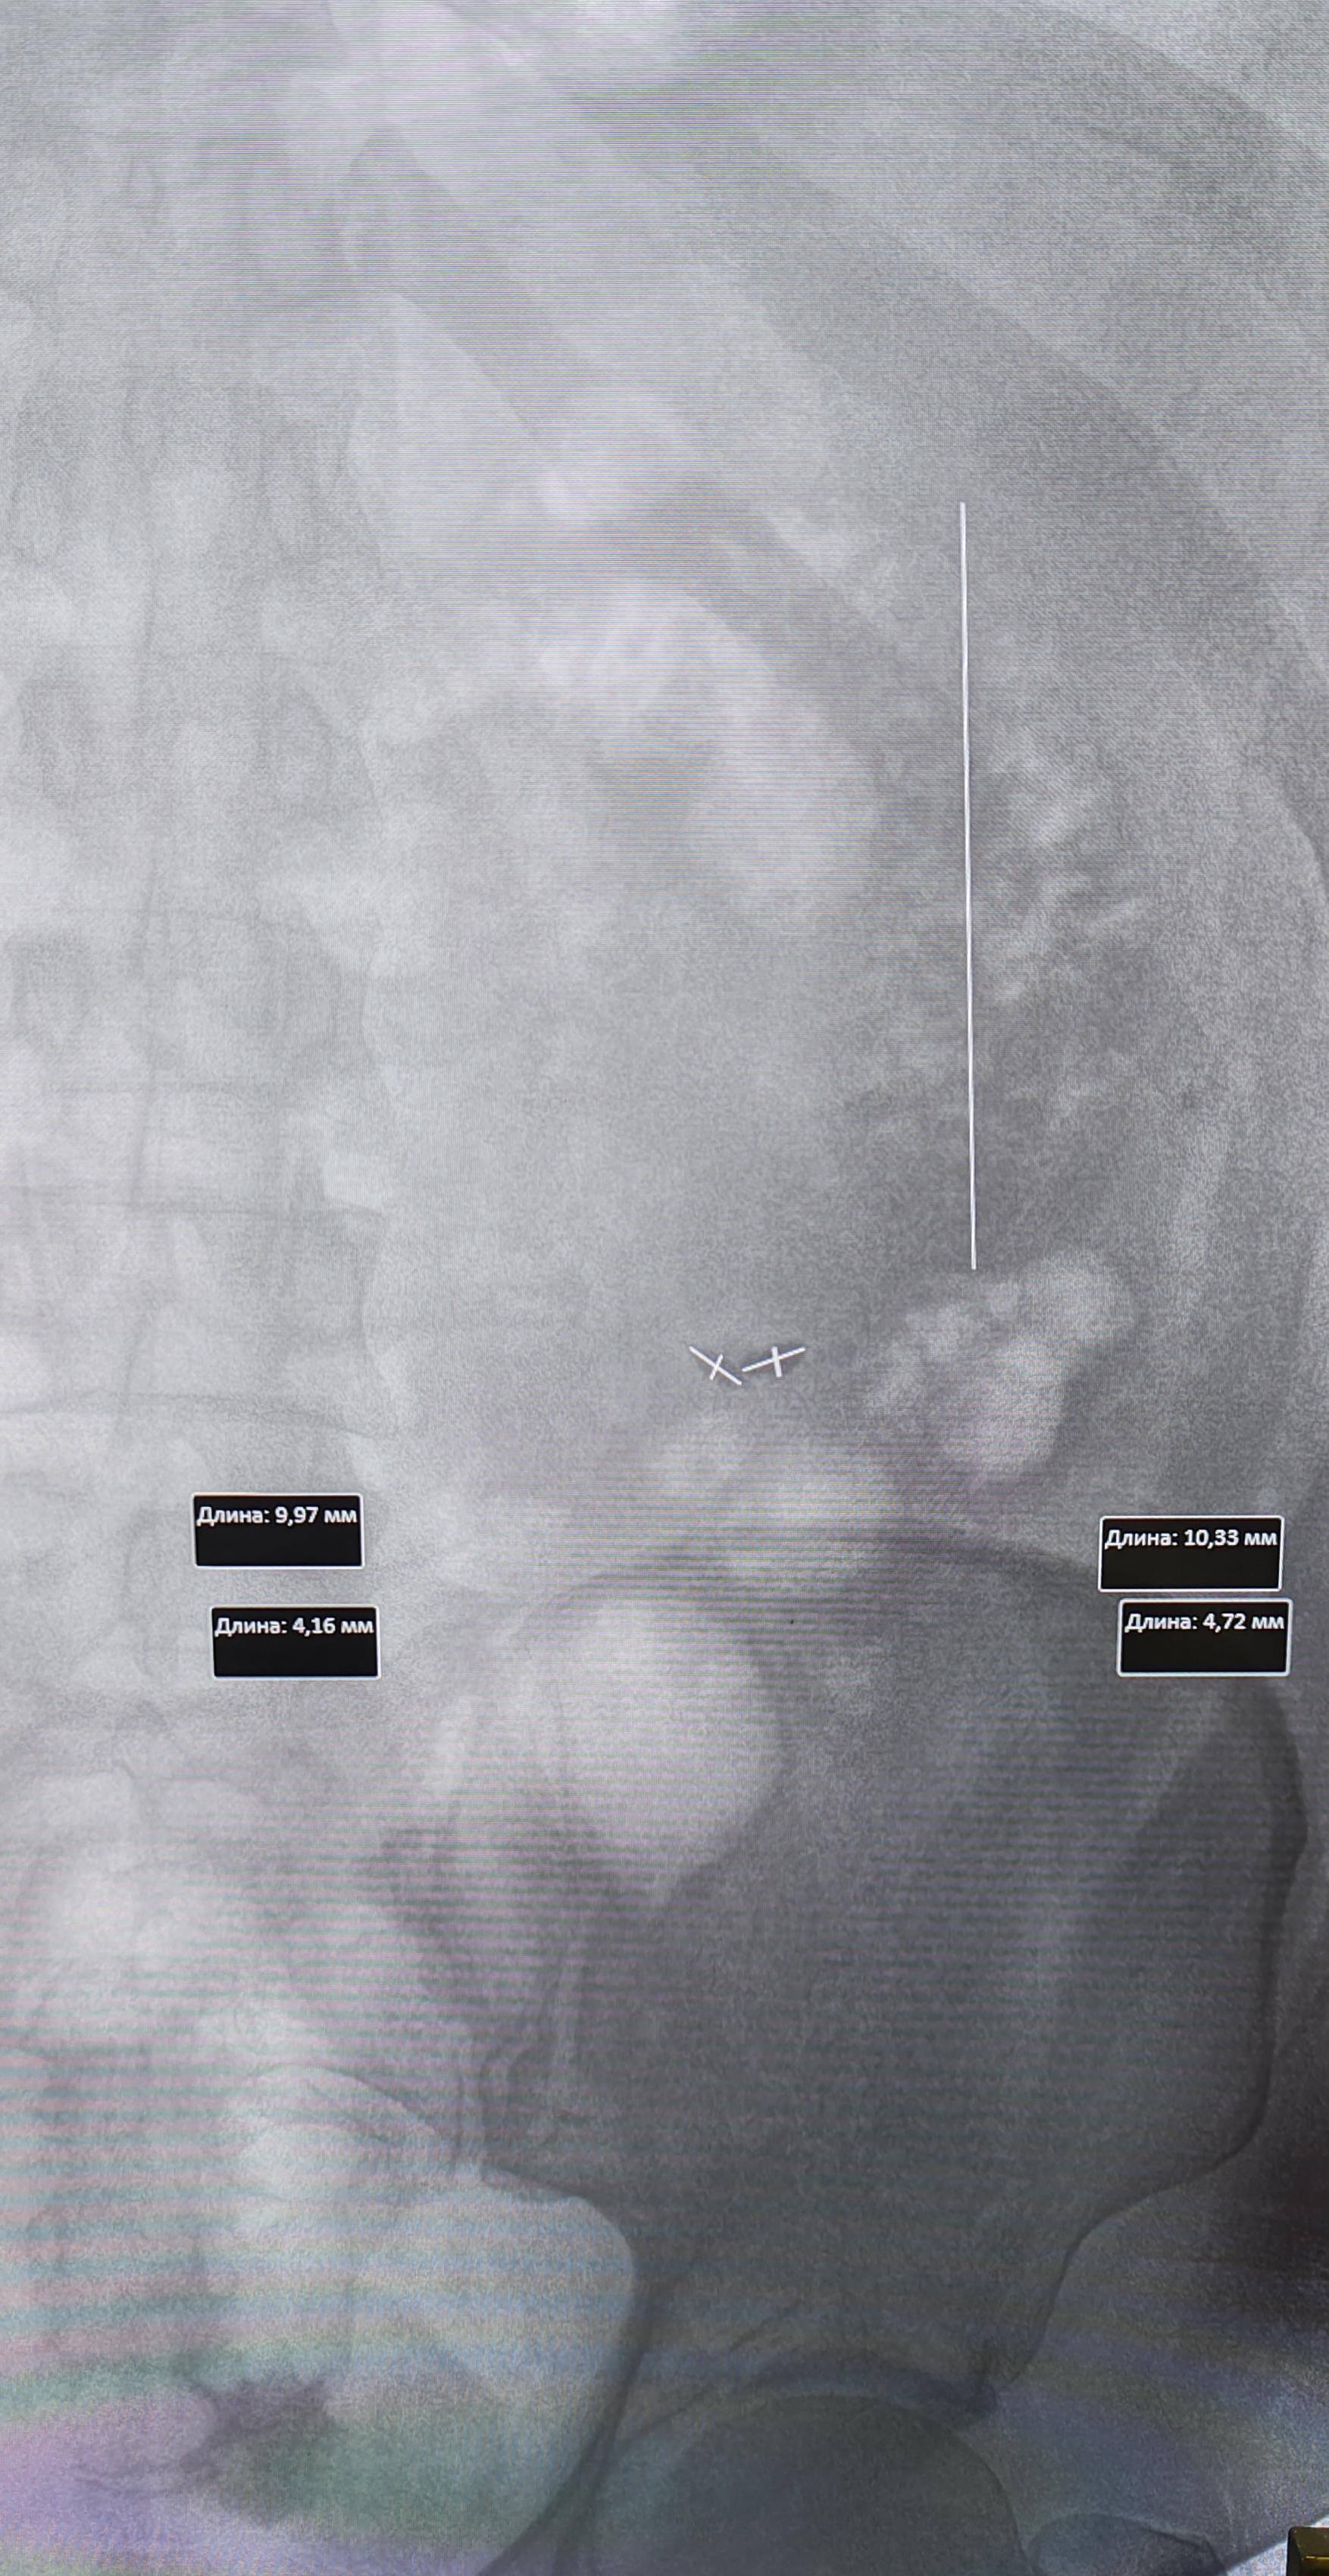

Описание: тени почек на уровне L1-L4 левая,L1-L4 правая, в ЧЛС левой почки определяются тени от множественных мелких конкрементов. В верхней трети левого мочеточника, ориентировочно 7.5мм от устья, визуализируются тени(N 2) от конкрементов, неправильной овальной формы, косо-горизонтально расположенные относительно мочеточника, размерами 10.3х4.7мм, 9.9х4.1мм.Заключение:Мочекаменная болезнь левой почки. Конкременты верхней трети левого мочеточника.